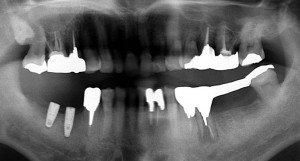

右下(写真では左下)6番歯根破折

右下(写真では左下)6番歯根破折

右下(写真では左下)に2本インプラント埋入 その後左下(写真では右下)5番歯根破折が起こった

右下(写真では左下)に2本インプラント埋入 その後左下(写真では右下)5番歯根破折が起こった